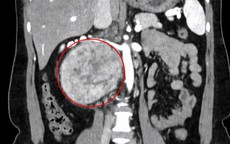

Dựa trên tình trạng sức khỏe và quy trình khám tổng quát, bác sĩ chỉ định chị C. thực hiện các xét nghiệm thường quy như siêu âm ổ bụng, tuyến giáp, tuyến vú. Tuy nhiên, trong quá trình siêu âm ổ bụng - một kỹ thuật đơn giản nhưng hiệu quả cao, bác sĩ đã phát hiện hình ảnh bất thường theo dõi u cơ mỡ mạch thận (Angiomyolipoma - AML) ở thận trái.

ThS.BSCKI Phạm Đặng Hoài Nam - Bác sĩ Y học gia đình cho biết, u cơ mỡ mạch thận là loại u lành tính phổ biến nhất của thận. Mặc dù lành tính, khối u có thể phát triển nhanh, gây chèn ép làm suy giảm chức năng thận hoặc khiến mạch máu giãn lớn dễ vỡ, dẫn đến xuất huyết nguy hiểm.

Ảnh minh họa.

U cơ mỡ mạch thận có mối liên quan với bệnh di truyền xơ cứng củ, thường xuất hiện với nhiều khối u ở cả hai thận, cũng có thể gặp ở phụ nữ mắc một số bệnh lý phổi hiếm gặp.

Các khối u nhỏ thường ít gây triệu chứng. Tuy nhiên, u có thể tăng kích thước đến 4 cm mỗi năm. Đặc biệt, u lớn hơn 5 cm hoặc có phình động mạch sẽ làm tăng nguy cơ vỡ mạch máu - một biến chứng cấp cứu, có thể đe dọa tính mạng. Theo nghiên cứu, nguy cơ xuất huyết tích lũy là 10% ở nam và 20% ở nữ.